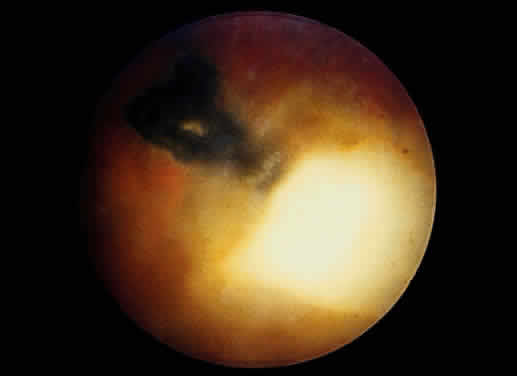

Bradyzoites are slowly metabolizing organisms found in cysts formed within the tissue of the infected host. The size of the Toxoplasma cyst varies, depending on the number of organisms that have multiplied within it. The cyst may reach more than 100 μm in diameter and may contain from 50 to 3000 organisms. The cyst wall is strongly argyrophilic and periodic acid-Schiff positive. It contains constituents that are derived from both the parasite and the host tissue. Constituent from the host tissue compose the outer part of the cyst, whereas those derived from the parasite are in the inner part of the cyst wall. Toxoplasmosis may be found in the inner layers of the retina after episodes of acute retinochoroiditis. The cyst may stay in the retinal tissue for years without showing any signs of invasiveness. Considering that the tissue cyst incorporates elements derived from the host into its outer wall, it is easily tolerated by the host, and no inflammatory reaction is seen around it (Fig. 2). It may remain for years in certain tissues, such as the eye or muscles, without provoking any inflammatory reactions. The bradyzoite inside the cyst derives its nutrition from the slow diffusion of substances through the cyst wall. The number of organisms increases within the cyst in the retina, and once the cyst wall breaks down by mechanical stretching, the bradyzoites escape, convert into tachyzoites, and invade contiguous cells. This process may lead to recurrence of retinitis. Certain immunologic mechanisms of the host may influence the organisms significantly. Immunosuppression coinciding with the rupture of the cyst and release of bradyzoites allows the organisms to become tachyzoites and proliferate in host tissue without restriction. The cyst of the Toxoplasma organism appears to be a defensive stage in its life cycle. The resistance of toxoplasmosis within chronically infected tissues of animals may lead to transmission of the disease by the ingestion of undercooked meat, including mutton, beef, pork, and chicken. Tissue cysts can develop within any organ and are commonly found in infected tissues of brain, eye, heart, skeletal muscles, and lymph nodes. Rupture of tissue cysts causes reactivation of the systemic toxoplasmosis in immune deficiency states, leading to dissemination of Toxoplasma organisms to other organs.